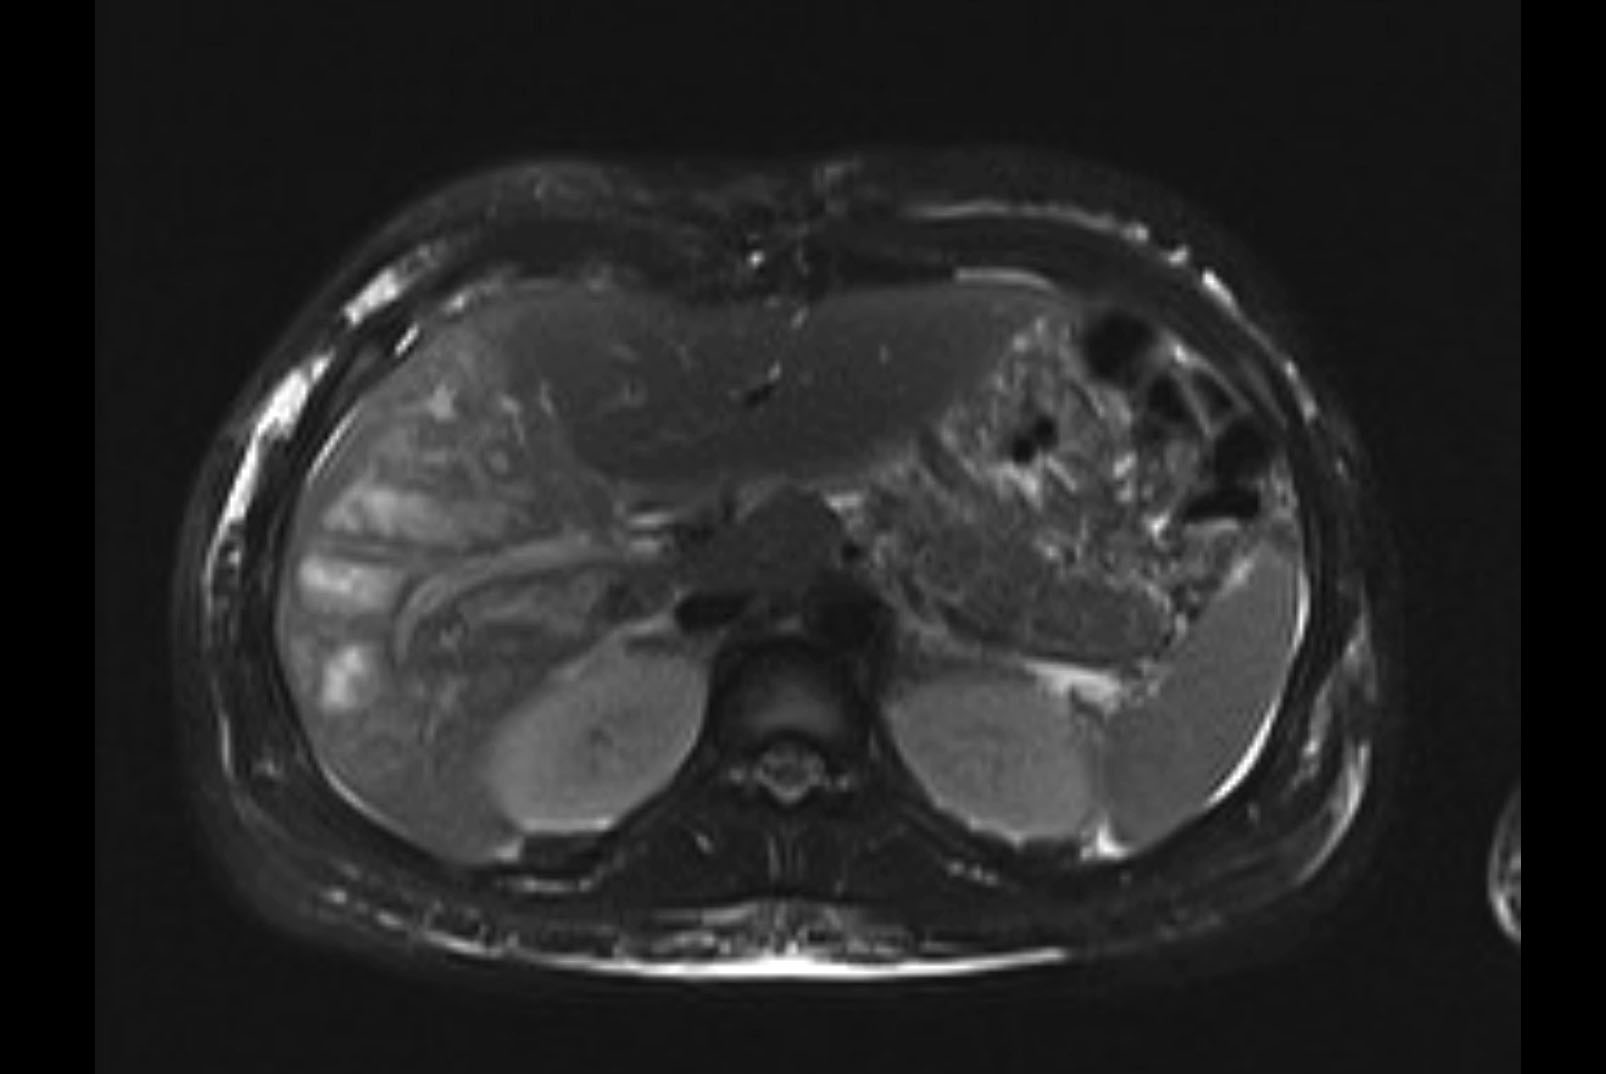

Imaging Analysis

Look through the patient's CT scan to identify any areas of concern for the necessary procedure.

MRI T1

MRI T2

Based on initial findings, which issue(s) would you be most concerned about?